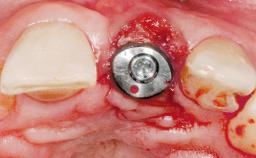

A 33-year-old female patient presented with an upper left central incisor that required extraction after a failed endodontic therapy. The tooth had been traumatized when the patient was a teenager and had undergone several endodontic treatments, including two apicectomy procedures. The patient was in good health and did not smoke. Clinical examination showed that the patient had a high lip line. In full smile, the gingival margins of the upper teeth were visible to the first molars. The gingival margins of central incisors 11 and 21 were only just showing. Examination of tooth 21 confirmed that the tooth was mobile and had hypererupted by 1 mm.

Type of Implants One-Piece

Bone Augmentation Horizontal|Simultaneous

Augmentation Materials Xenogenous|Membrane

Soft Tissue Grafting Simultaneous

Placement Protocol Immediate implant placement

Socket Integrity Damage to one or more bone walls

Bone Volume Damage to one or more socket walls